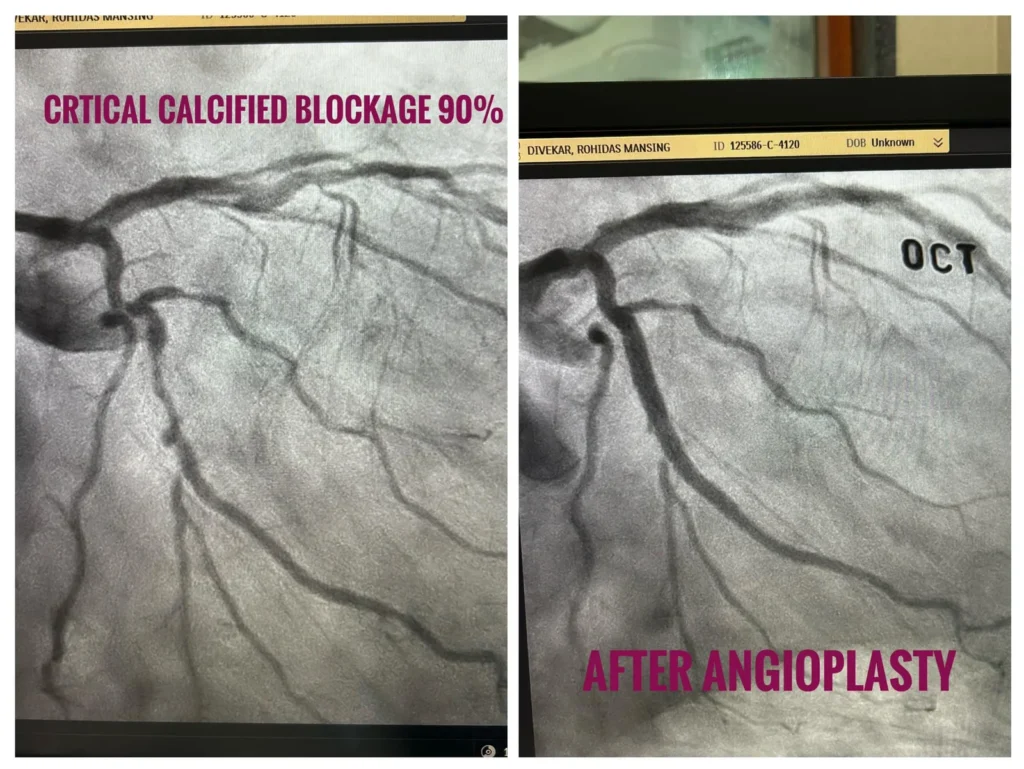

Successful OCT-Guided Angioplasty for Critical Triple Vessel Disease & LAD Aneurysm